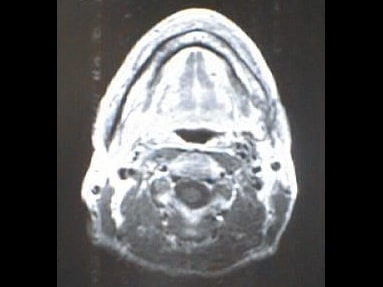

中咽頭末期がんMRI画像②

入院当時MRI画像②

中咽頭末期がん消滅時MRI画像②

入院3か月後癌消滅MRI画像②

中咽頭末期がんMRI画像③

入院当時MRI画像③

中咽頭末期がん消滅時MRI画像③

入院3か月後癌消滅MRI画像③

中咽頭末期がんMRI画像④

入院当時MRI画像④

中咽頭末期がん消滅時MRI画像④

入院3か月後癌消滅MRI画像④